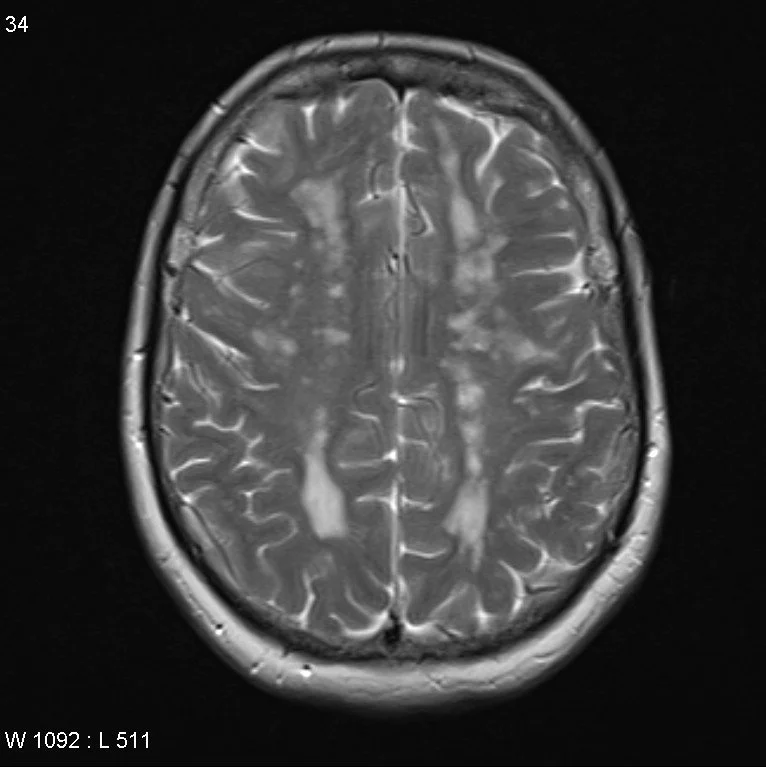

Cerebral Autosomal Dominant Arteriopathy with Subcortical Infarcts and Leukoencephalopathy (CADASIL)

• Autosomal dominant mutation in NOTCH 3 gene causing vasculopathy which results in recurrent ischemic infarcts and eventually vascular dementia

• This is basically early onset multi-infarct dementia

• Age 30-50 = TOO YOUNG FOR DEMENTIA AND RECURRENT STROKES

• Imaging

• Confluent white matter T2 hyperintensities

• Temporal lobe and external capsule are classic locations

• Occipital lobe and cortex are typically spared